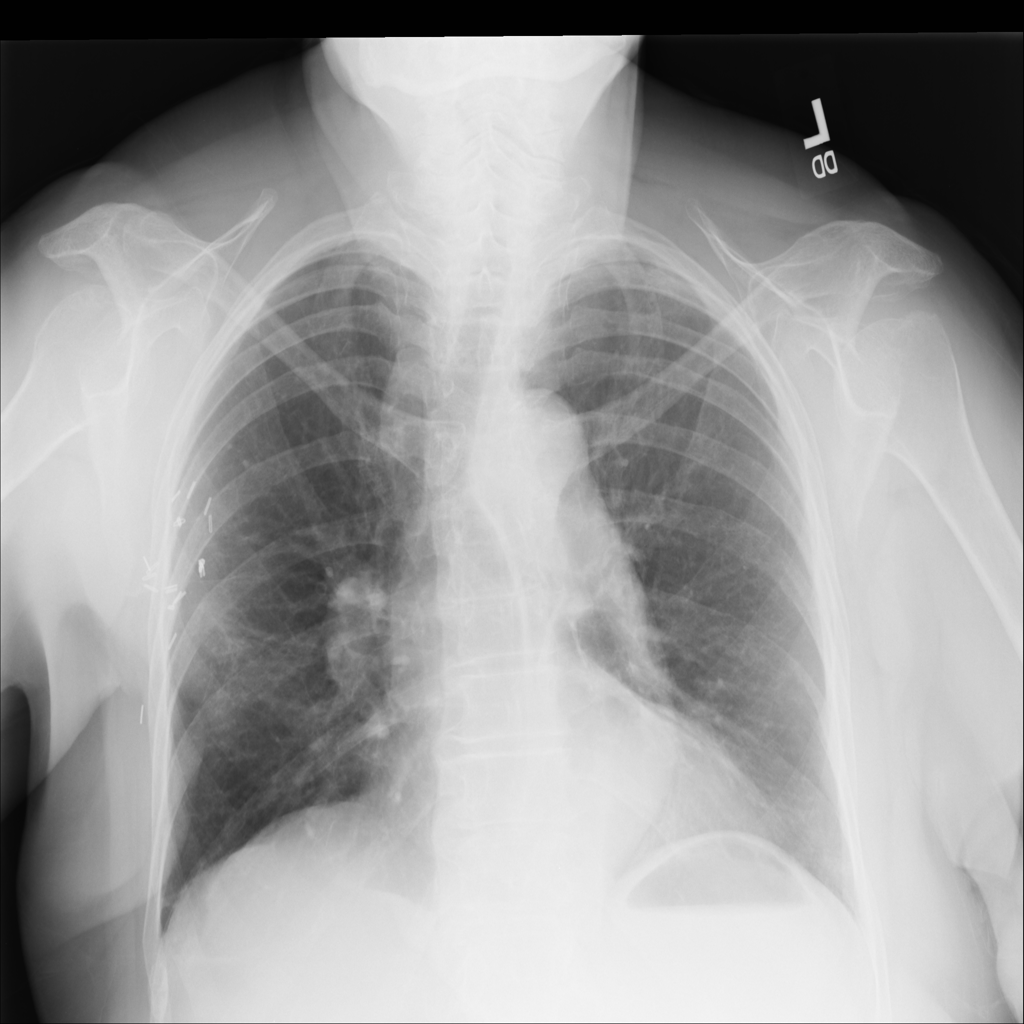

PAT-AE5C · IMG-000Cardiomegaly

PAT-AE5C · IMG-000

PA